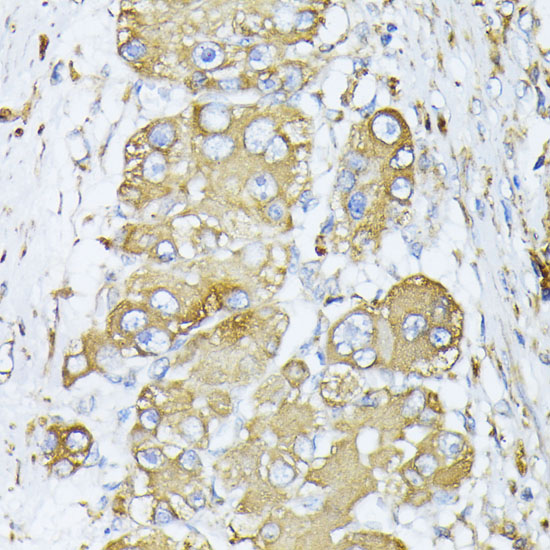

ApplicationWB, IHC